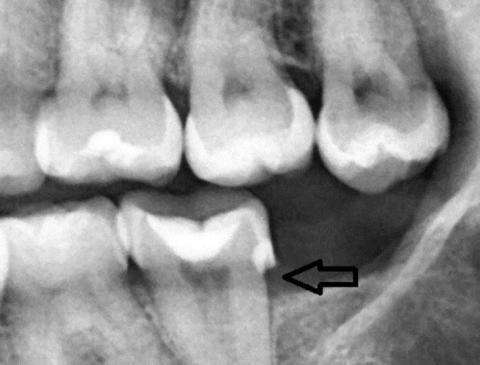

Focused Area: Posterior teeth (molar region) with interproximal defect indicated by arrow

Radiolucent area between posterior teeth, consistent with interproximal dental caries

Possible loss of tooth structure at the contact point

Early signs of localized bone level reduction adjacent to the affected tooth

Existing restoration visible on the molar, suggesting previous decay history

No obvious advanced periapical abscess visible at this image depth, but early pathology cannot be ruled out

Interproximal dental caries (moderate depth)

Early periodontal bone involvement localized to the molar region

Increased risk of pulp irritation depending on cavity depth